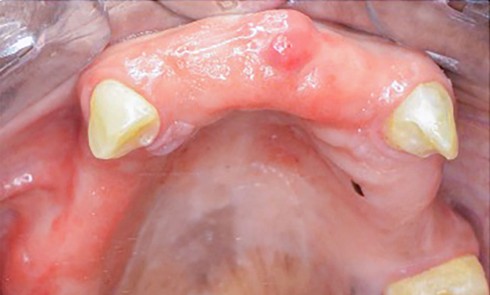

Article réservé à nos abonnés Impact des tabacs fumés et non fumés sur la muqueuse buccale et le parodonte

Les différents modes de consommation Le tabac est préparé différemment selon la façon dont il est consommé. Les tabacs fumés Les tabacs...